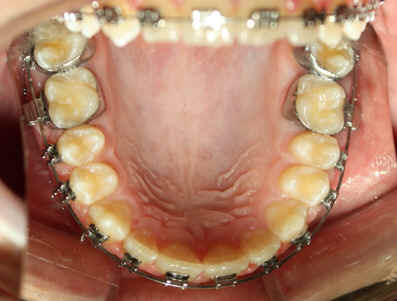

2009/10/31 U .016x.022, L to be .016 Niti

2009/12/19 U .016x.022, L .016 x .022 Niti